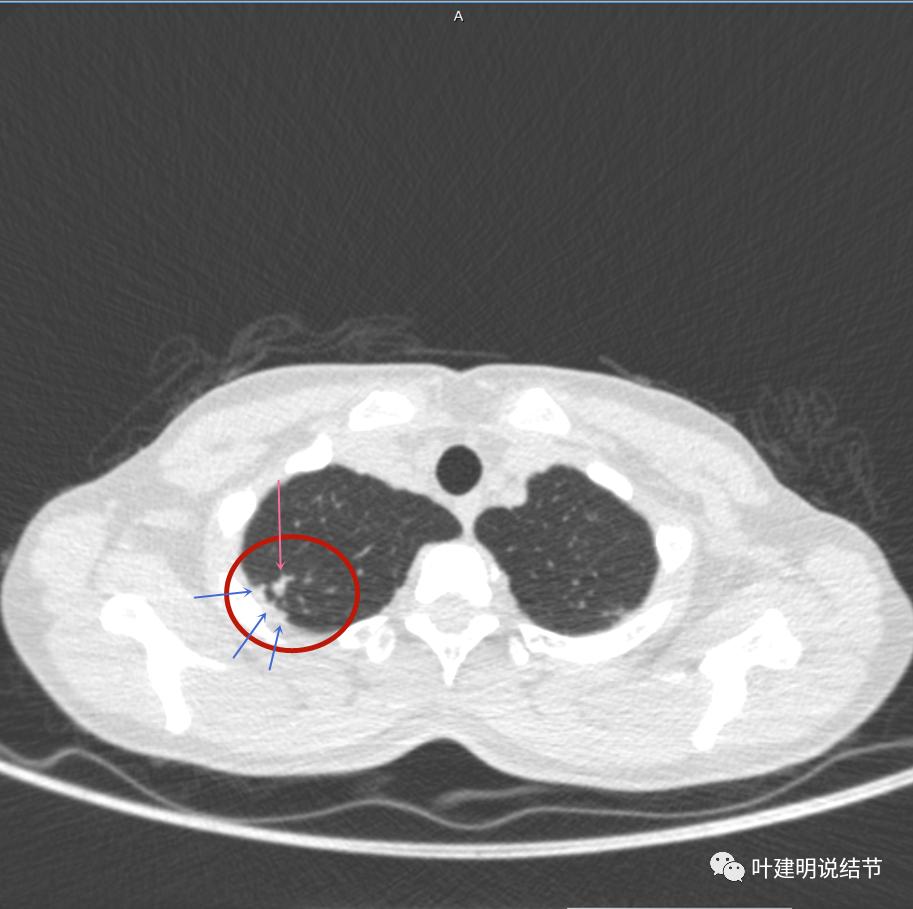

有卫星病灶(绿色箭头)

胸壁侧病灶较厚,模糊(蓝色箭头),仍见卫星灶(绿色箭头)